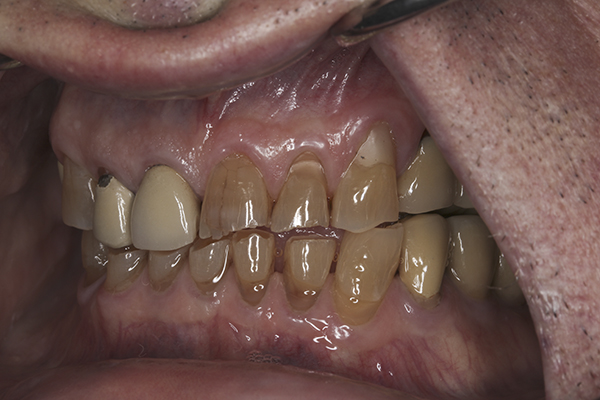

(10.) Preoperative anterior, closed view. Note the end-to-end occlusion of the anterior teeth and the wear on the incisors and centrals resulting in no anterior or canine guidance.

Figure 10

(11.) Preoperative left lateral, closed view.